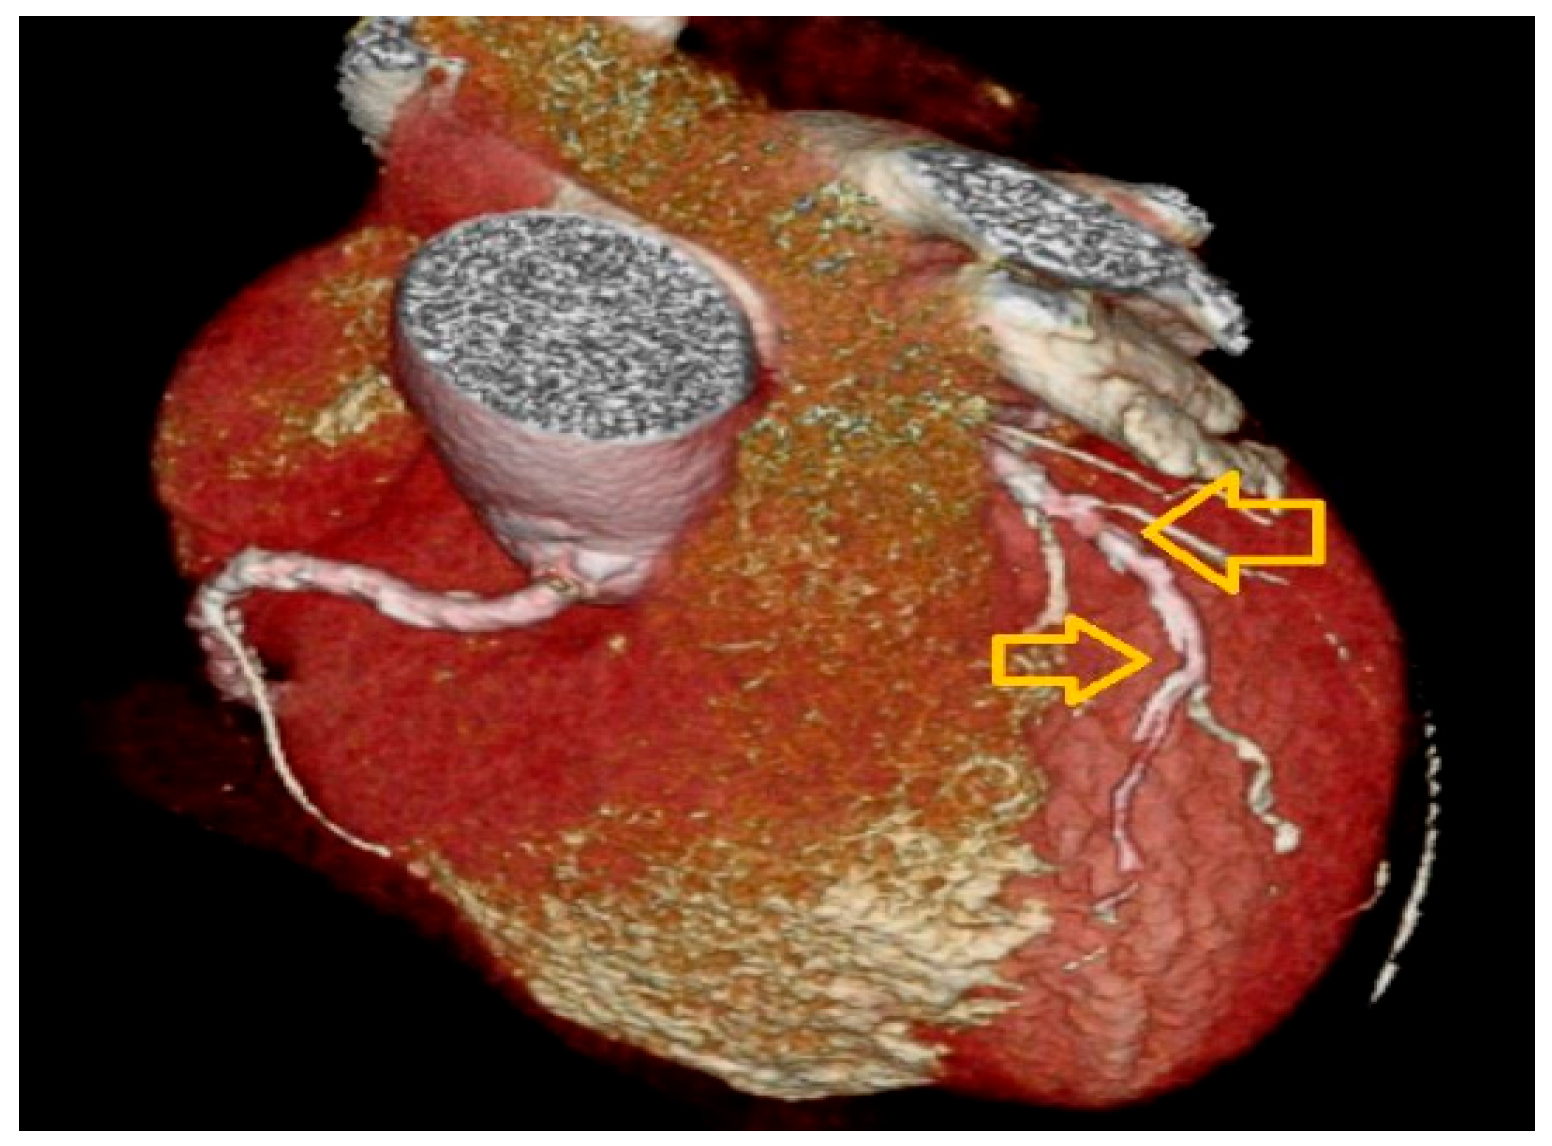

| Presence of coronary plaque, n (%) | 15 (20.3) | 8 (7) | 0.015 a |

| Percentage of stenosis, median (IQR) | 40 (25–52) | 45 (40–60) | 0.330 b |

| Coronary stenosis > 50%, n (%) | 4 (28.6) | 4 (50) | 0.386 a |